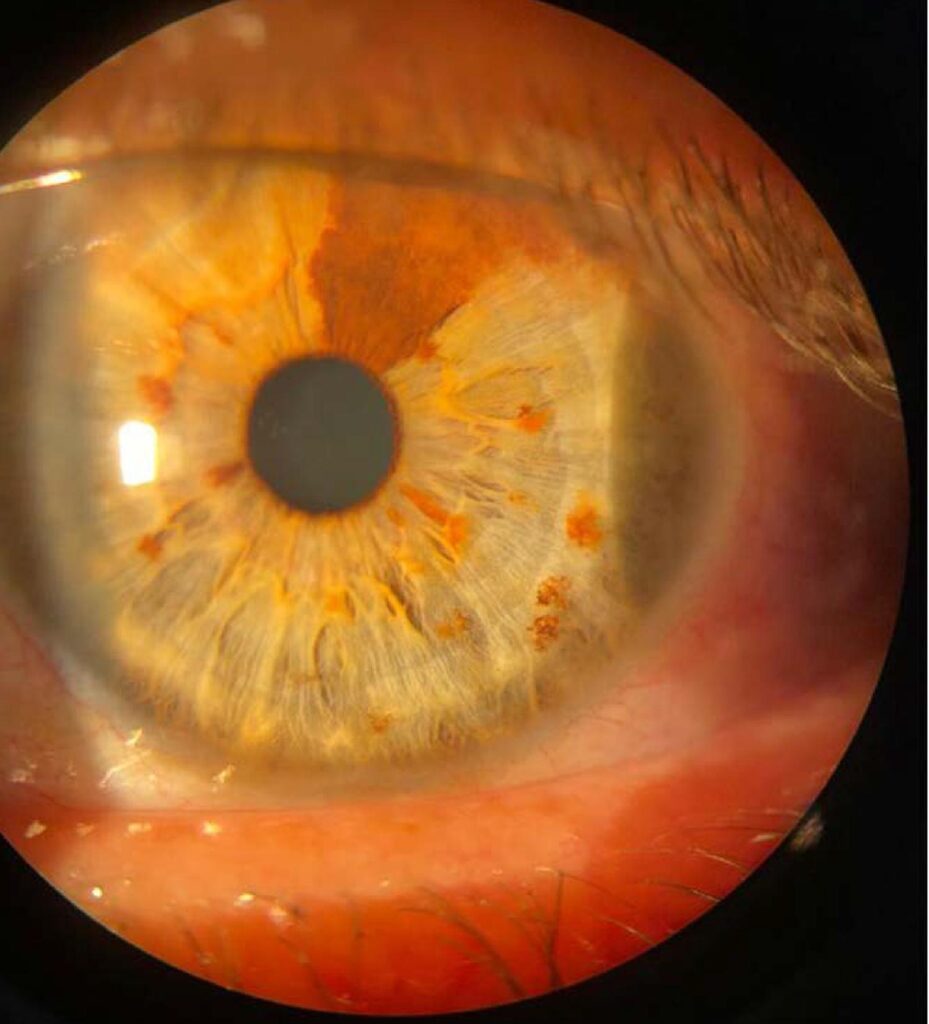

A íris é responsável pela cor dos olhos. Ela ainda realiza o controle da quantidade de luz que penetra no olho pela pupila. Variações nos genes de cada indivíduo, além da quantidade e da qualidade de melanina na íris, determinam a cor dos olhos. A heterocromia é caracterizada por diferenças na coloração da íris de um mesmo indivíduo, sendo, na maioria das vezes, benigna. Existem basicamente três tipos de heterocromia de íris: central, setorial e completa. A heterocromia de íris pode ter como causa alterações genéticas e congênitas, relacionadas ou não a síndromes específicas, como a de Sturge-Weber, a de Waardenburg, a de Parry-Romberg e a de Horner congênita. Há também causas adquiridas, como doenças ou lesões, trauma ocular e corpos estranhos intraoculares, uso de certas medicações tópicas, siderose ocular, irites ou uveítes como a síndrome uveítica de Fuchs, dentre outras. Diante de um paciente com heterocromia de íris, deve-se entender o contexto e o curso clínico desse sinal, pois pode se tratar de uma alteração de pigmentação benigna ou existir uma doença base em curso, que requer terapêutica específica. Este artigo de revisão de literatura visa abordar as principais etiologias relacionadas à heterocromia de íris, além de discorrer sobre a anatomia e a fisiologia da coloração iridiana e sobre a fisiopatologia de suas possíveis alterações.